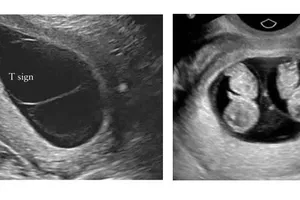

Việt Nam có ca song thai hiếm, cùng trứng nhưng khác giới tính và gene Y tế - Sức khỏe 09/11/2022 20:20